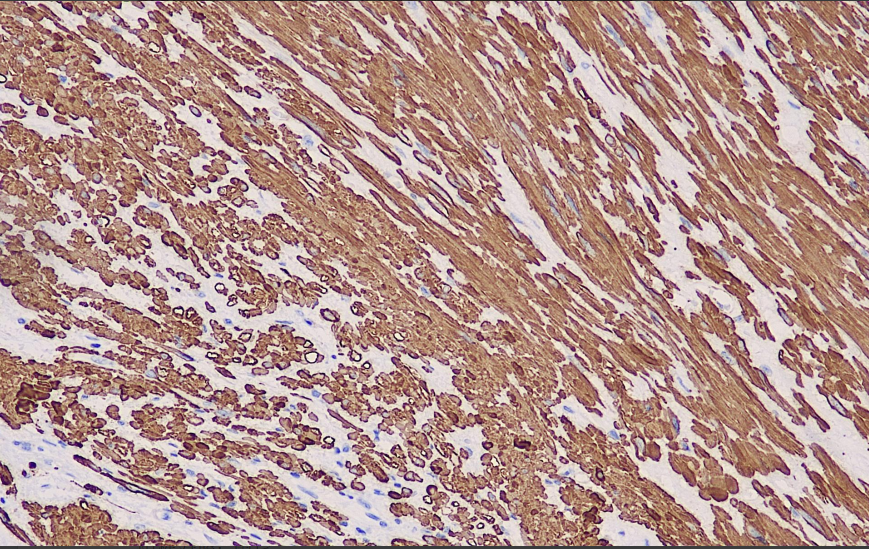

Actin is a microfilament protein with the ability to contract and is a major component of the myocyte cytoskeleton. Actin can be classified into three types according to its isoelectric point from low to high: alpha, beta, and gamma.MSA recognizes alpha actin and gamma actin in skeletal, cardiac, and smooth muscle. It can be used in the study of skeletal, cardiac and smooth muscle and tumors of their origin. Non-muscle cells such as vascular endothelial cells and connective tissue do not react with it. Therefore, tumors of non-muscle origin such as epithelial tumors, melanomas, and lymphomas are negatively tabulated for this antibody.

Actin Antibody Reagent binds specifically to Actin molecular antigen. Immunohistochemistry kits containing Actin Antibody Reagent are indicated for the precise diagnosis of tumors of skeletal, cardiac and smooth muscle and their origin.